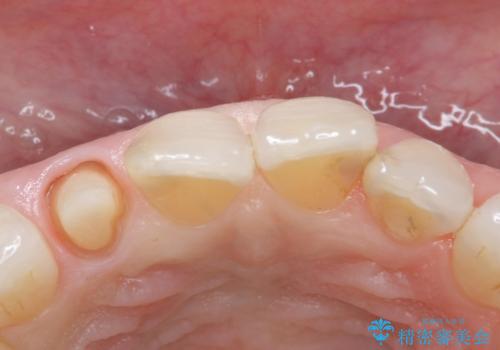

- 右上の前歯が取れたとのことで来院された患者様です。

再根管治療からのやり直しをご提案しましたが、ご希望されなかったため土台(コア)のやりかえからとなりました。

- 右上2 仮歯/11,000円 ファイバーコア/22,000円 ジルコニアクラウン(スペシャル)/154,000円 合計187,000円費用は治療当時の料金となります